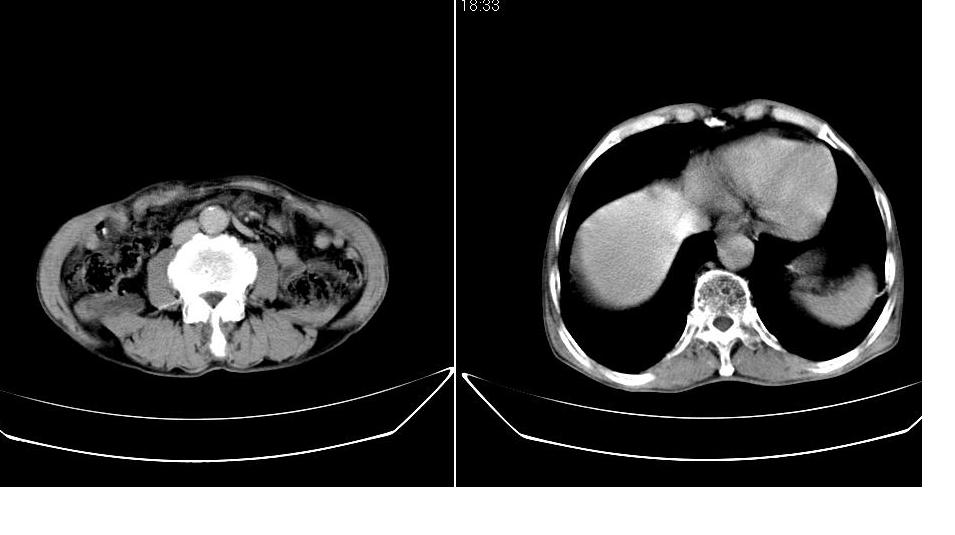

男,76岁,上腹部疼二天来就诊,彩超提示肝左叶占位,随后做上腹部ct平扫,今天做上腹部ct增强扫描,手工推药,效果不好,请谅解。

肝左叶s4肿块强化形式大概是:慢进慢出,逐渐强化----考虑血管瘤/腺瘤?{动脉期应更提前扫}。

肝右叶前段hcc

1)肝右叶前段低密度灶,不排除肝癌可能;建议查afp。2)右肾上极囊肿。

肝内胆管积气扩张,胆囊增大,肝右前叶低密度灶,逐渐强化,一元论,胆系感染,局限性肝脓肿;右肾囊肿。

考虑肝s4段肝脓肿可能?未排除肝癌。右肾上极囊肿。